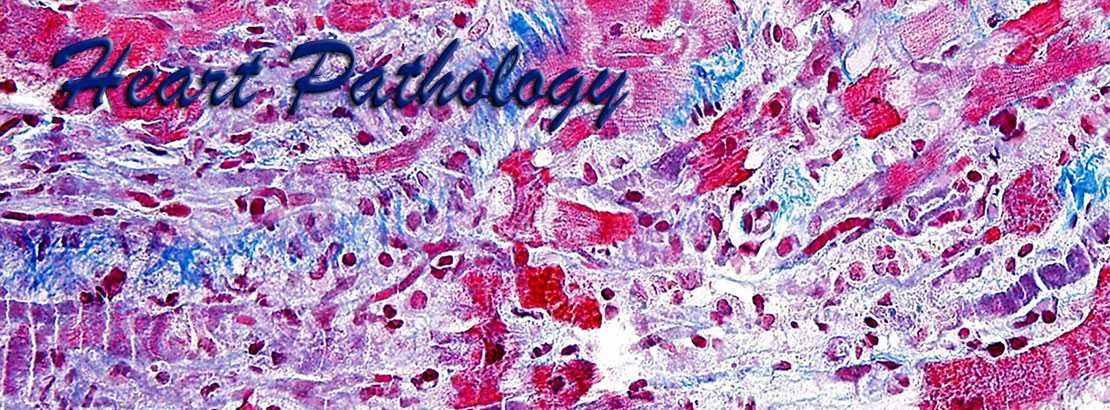

Cardiac pathology is an important area of pathology but is not comprehensively taught at many medical centers due to the paucity of cardiac specimens outside of the autopsy services. Our website uses high definition images obtained from gross pathology specimens and histological slides, both at a resolution of 1800x1350 pixels. Most images have been obtained using Olympus digital cameras.

The images presented here represent a wide variety of heart pathology cases, including acquired diseases, transplantation pathology, idiopathic diseases, tumor pathology, etc., and are accompanied by brief morphological descriptions. The histological images are shown at different optical magnifications and include conventional stains such as hematoxylin-eosin, PAS, trichrome stains, as well as immunohistochemical stains. Also included are some images from normal tissues and from positive and negative controls for the corresponding special stains.